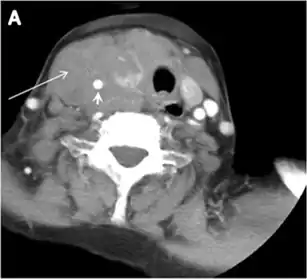

- Fig. 13. A 27-year-old female patient known to have goiter. a, b Axial and sagittal enhanced CT scan images of the neck demonstrate a heterogeneously enhancing, enlarged thyroid gland with scattered calcifications (white arrow), cystic changes, and substantial retro-sternal extension (black asterisks). No lymphadenopathy or substantial airway narrowing.[1]

Malignancy can coexist within the goiter and a CT scan may give a clue if there are abnormal cervical lymph nodes and/or signs of invasion. Retrosternal extension (Fig. 15) could affect the surgical approach, as a lower extent may require a partial or total sternotomy to facilitate complete resection. Therefore, the distance of the retrosternal extent from the sternal notch should be measured on a sagittal image.[1]